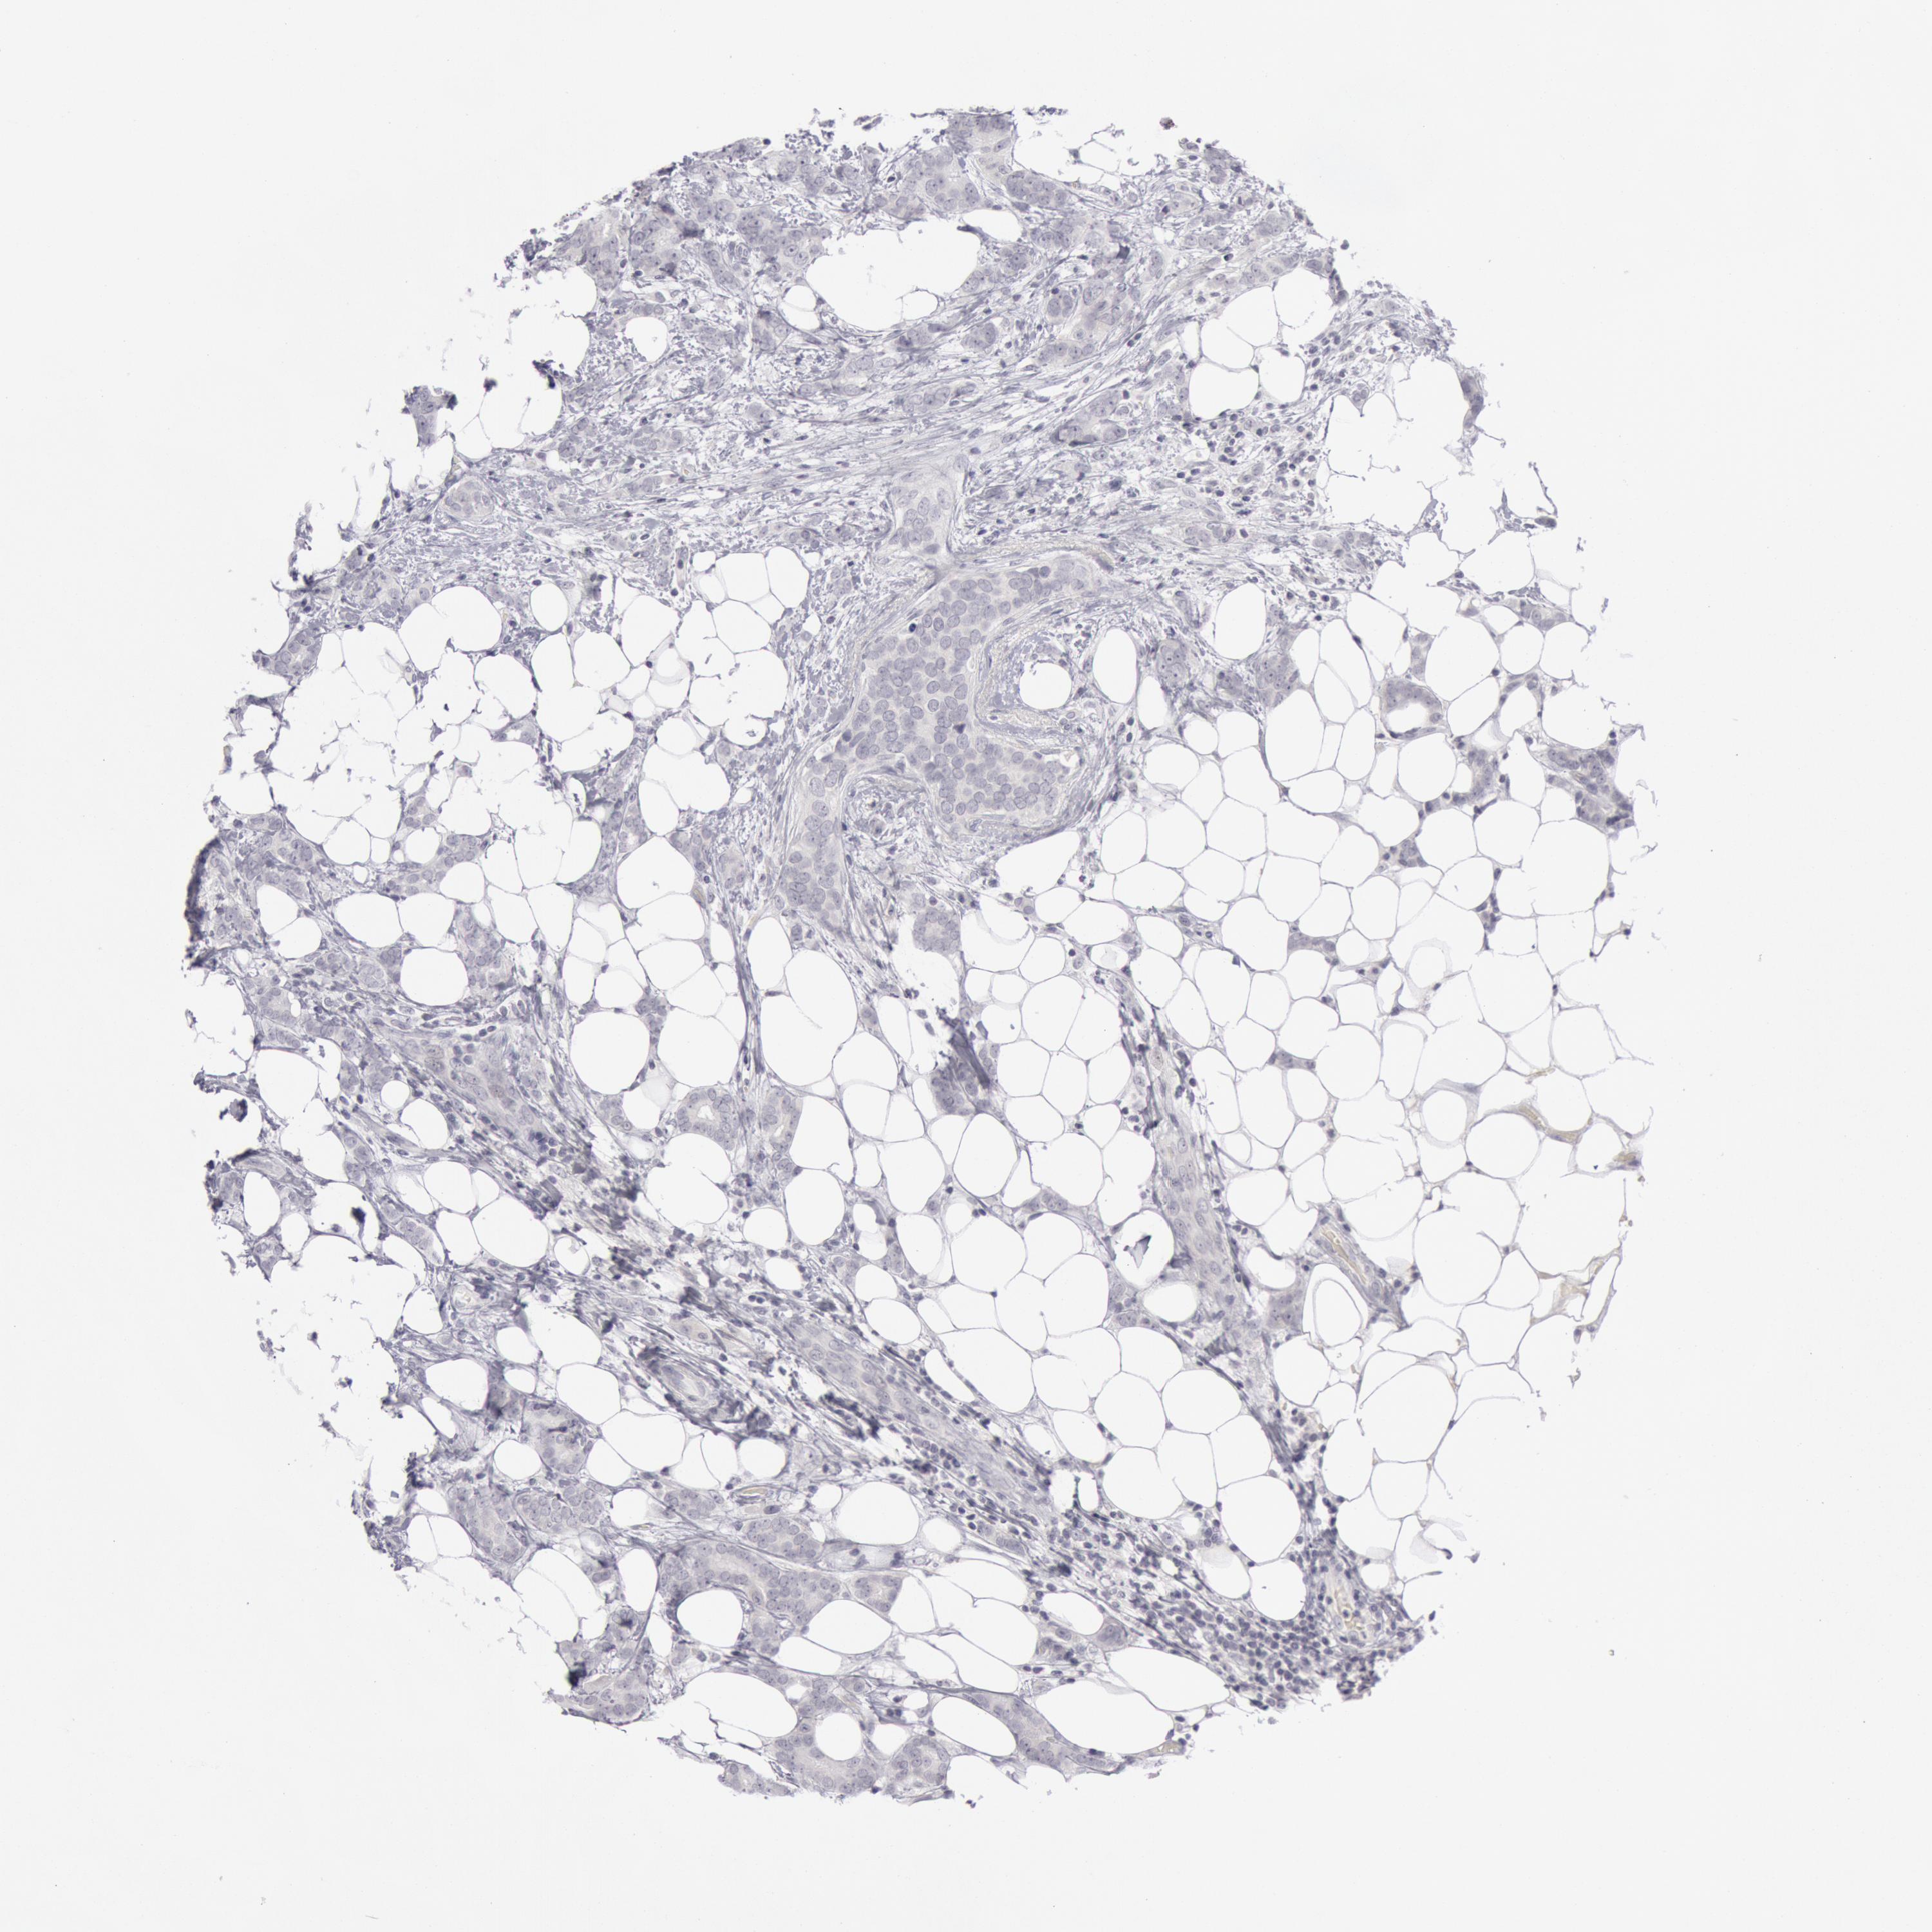

BRCA TCGA BRCA VALIDATION PROTEIN EXPRESSION